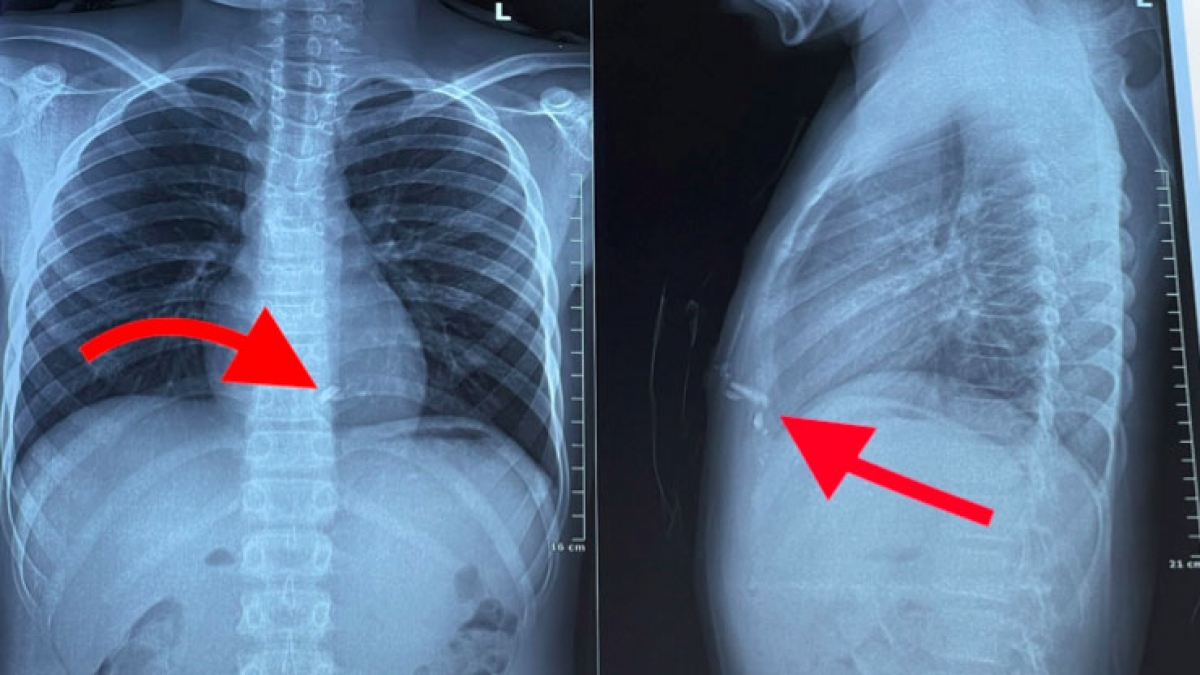

Chụp phim X-quang ngực thấy có 2 dị vật kim loại trong lồng ngực nằm sau xương ức bên trái, nghi ngờ tổn thương tim. Các bác sĩ đã nhanh chóng mổ cấp cứu kịp thời lấy dị vật, khâu vết thương thành thất phải cho bệnh nhân.